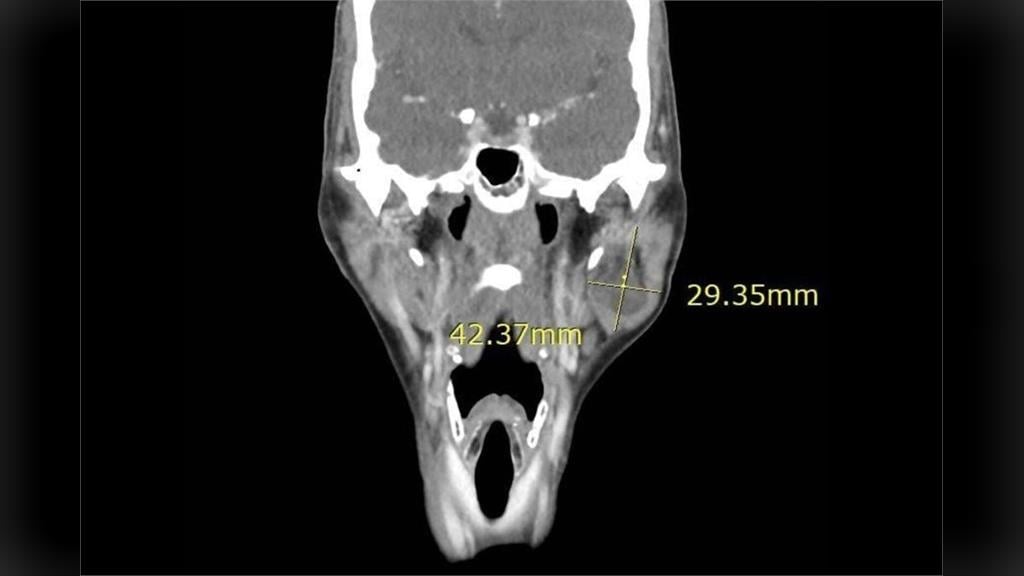

CNEWS匯流新聞網記者陳鈞凱/台北報導左臉突然「凸」一塊!56歲的陳女士,2年前突然發現左側臉頰有莫名突起腫塊,大小足足有4公分,嚴重影響外觀,讓她變得沒有自信,在網路上反覆自行查詢相關資料後,擔心手術後臉部恐留下明顯凹陷,因此遲遲不敢就醫,直到輾轉就醫才發現是腮腺癌中的腺細胞癌第二期。醫師提醒,一旦發現兩頰出現不明腫塊,應盡早尋求專業醫師診斷,以免延誤治療時機。

收治病人的台北慈濟醫院耳鼻喉科醫師蔡祐任表示,陳女士就醫時,進一步抽吸及影像學檢查發現為腮腺腫瘤,考量外觀影響及腫瘤有惡性可能,決定透過腮腺切除手術,取出腫瘤及腮腺並利用頸部旋轉皮瓣進行修補。